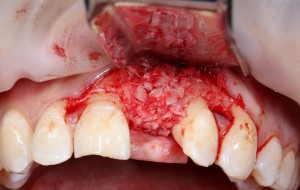

А в качестве трансплантата — аутокостная стружка, которую я насобирал заранее из области угла нижней челюсти:

Начну с того, что BioGide — это лучшее, что есть сейчас на рынке, а остальные мембраны ей завидуют. Как и в случае с макродизайном имплантов, именно физические свойства определяют как удобство использования, так и возможность достижения нужного результата. Прочность, эластичность, легкая адаптация и адгезия делают ненужными использование фиксирующих пинов. Мы просто закрываем мембраной графт — и все, можно накладывать швы:

В другом ракурсе видно, какой объем тканей мы восстанавливаем:

и теперь швы. Наглухо (Фактор II):